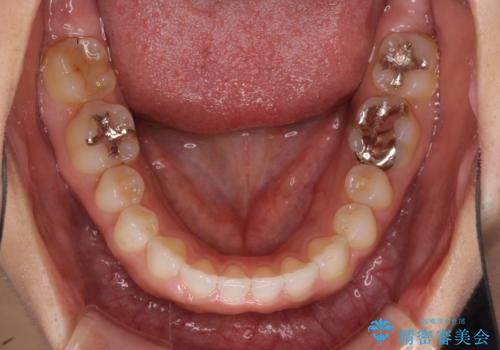

- 前歯の隙間を気にして来院された患者様です。

隙間、捻転ともに軽微でありましたが、下顎前歯の突き上げにより隙間ができていたため、インビザラインを用いて咬み合わせを改善しながら前歯の歯列を整えていくこととしました。

当初は1年程度で終えられると思いましたが、治療途中から装着時間が短くなったり、来院間隔が長期になったりとし、結果として4年半以上の治療期間となりました。